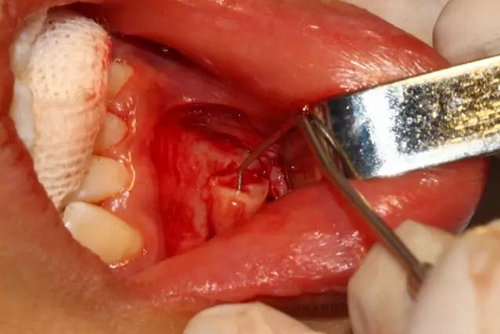

去除含牙囊壁

創(chuàng)口處理

創(chuàng)口內(nèi)置入膠質(zhì)銀明膠

關(guān)閉創(chuàng)口、對位縫合